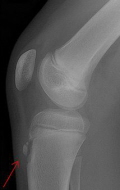

Common Running Injuries (the lower leg bone), just below the knee. The patient will most likely notice pain on the lower portion of the patella or just below it. Pain may also be felt on the upper part of the patella or on the tibia at the tendon’s attachment site. ... Fetch Doc

Anterior Knee Pain - Plymouth Hospitals

Anterior Knee Pain What is Anterior Knee Pain? Anterior knee pain is characterised by pain felt at the front of the knee over the knee cap (patella). It is more common in adolescents and healthy young It is an overuse injury and pain is felt just below the patella. ... Fetch Content

This can be painful to touch just below the patella (knee cap) either side of the tendon. then physiotherapy and rehabilitation. SPRAIN to Lateral Collateral Ligament (LCL) side of the knee and leg into the hip. Pain normally occurs during running and disappears ... Fetch Document